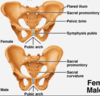

delineate the general areas of the: ___ ilium ___ ischium ___ pubis

___ ant sup iliac spine (ASIS) ___ ant inf iliac spine (AIIS) ___ posterior superior iliac spine (PSIS)

___ pubic tubercle & crest ___ obturator foramen ___ auricular /articular surface of SI joint

___ iliac tuberosity

___ iliac fossa ___ pubic symphysis

___ ischial tuberosity ___ greater sciatic notch

___ lesser sciatic notch ___ ischial spine ___ acetabulum

_ sacrotuberous ligament

_ sacrotuberous ligament